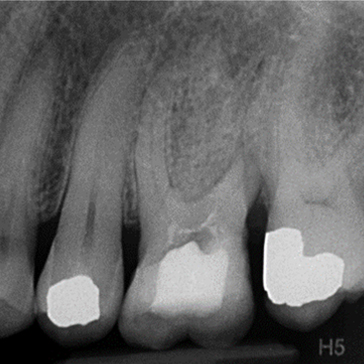

Case 4. Re-RCT of LR6